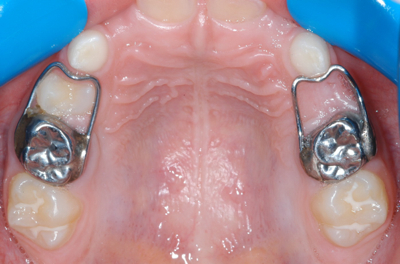

20130330a-casoA melhor forma de prevenir a perda de espaço é mediante a utilização de mantenedores de espaço, o que pode prevenir ou diminuir o aparecimento de maloclusão.

Na literatura científica encontramos numerosas referências sobre indicações, contra-indicações, desenho, controlo e pautas de seguimento dos mantenedores de espaço para que estes realizem a sua função mas sem interferir no crescimento e desenvolvimento da oclusão.

Nesta apresentação serão realçadas as indicações dos mantenedores de espaço, bem como os vários tipos de dispositivos disponíveis.